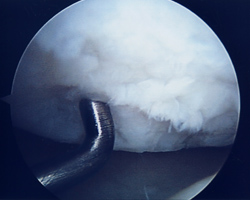

Abb. 3: 3b° Knorpelschaden nach ICRS, traumatisch bedingt

Findet sich hingegen ein umschriebender Knorpeldefekt mit freiliegendem Knochen, so kann eine Mikrofrakturierung (MFx) durchgeführt werden. Hierbei wird zunächst der Rand des Knorpeldefektes stabilisiert, anschließend wird mit einem Sporn (Chondropick) mehrere gewollte Läsionen in Form einzelner Löcher in den Defekt gesetzt. Es kommt zu einer Blutung in den Defekt. Hierbei können sich sog. pluripotente Stammzellen im Defekt festsetzen und so einen Ersatzknorpel (Faserknorpel) bilden. Hierzu ist jedoch, um das OP Ergebniss nicht zu gefährden, eine bis zu 6 Wochen dauernde Entlastung des Kniegelenkes notwendig.  Eine begleitende krankengymnastische Behandlung sollte durchgeführt werden.